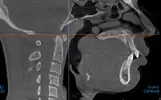

See how the OP and MPA are closely related - this allows for more CCW rotation during bimax.

See how the OP and MPA are closely related - this allows for more CCW rotation during bimax.